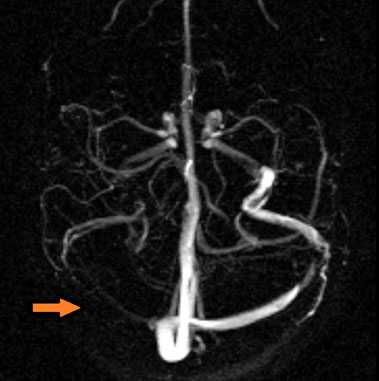

МР-венография - отсутствие визуализации кровотока в правом поперечном синусе и яремной вене.

МР-венография: тромбоз левого поперечного синуса. Отмечается потеря МР-сигнала от левого поперечного синуса.

МР-венография: тромбоз правого поперечного синуса. Отмечается потеря МР-сигнала от правого поперечного синуса.

МРА-картина выраженной асимметрии венозной сети с преобладанием и нерезкой дилатацией вен правой гемисферы (поперечного, сигмовидного синусов и яремной вены справа); гипоплазии левого поперечного и сигмовидного синуса. Единичные участки (2) локального расширения вен в парасагиттальных отделах левой гемисферы, большой вены мозга. Асимметричная, расширенная и выражено извитая венозная структура экстракраниальных отделов справа.

МРА признаки незначительной дилатации верхнего сагиттального синуса, локального снижения кровотока и сужения просвета дистальных отделов прямого синуса; асимметрии просвета поперечных, сигмовидных синусов и внутренних яремных вен.